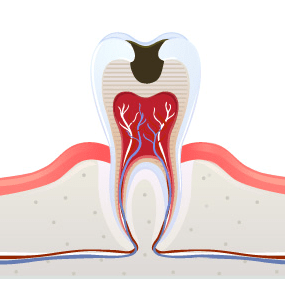

2 상아질 경계와 상아질까지

진행된 경우충치 부위를 삭제한 후

삭제 부위에 ‘인레이 치료’ -